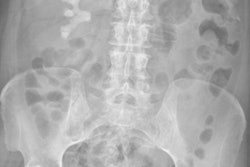

It's an old adage that a picture is worth a thousand words. This seems to hold true for radiology, where patient photos can help decrease patient misidentification errors, researchers reported at the Society for Imaging Informatics in Medicine (SIIM) meeting.

Researchers from Emory University have created a prototype of an Android-based camera device that can take digital photos of patients at the time they're being imaged and then integrate them within the PACS environment. A clinical observer study with the prototype showed a significant increase in radiologist detection of misidentification errors.

Misidentification of patients is a major problem in medicine, and radiology is no exception, Tridandapani said. Published research has reported detection rates for errors (misidentification or mislabeling) in imaging exams ranging from 0.26% to 0.73%. The actual error rate is likely even higher, he said.

In the first phase, 10 recently board-certified radiologists were each provided with a worklist for 20 pairs of radiographs without patient photographs. Unbeknownst to the readers, the pairs included two to four misidentification errors. The same 10 readers were asked to read 20 other pairs of radiographs, but this time with patient photos included. No additional instructions were provided.

Of the 24 total errors in the first phase of the study, only three errors (12.5%) were detected. When asked to read the pairs that included patient photographs, the readers detected 16 of 25 errors (64%).